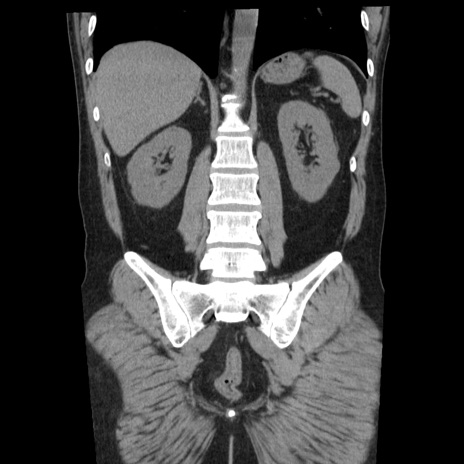

症例29(冠状断像)

【症例】40歳代男性

【現病歴】2日前から胃痛あり。徐々に周期的な激痛に変化した。本日になっても激痛があるため受診。

【身体所見】意識清明、BT 38-39℃台あり、腹部:膨満、やや硬、右下腹部に圧痛あり。

【データ】WBC 8500、CRP 23.26